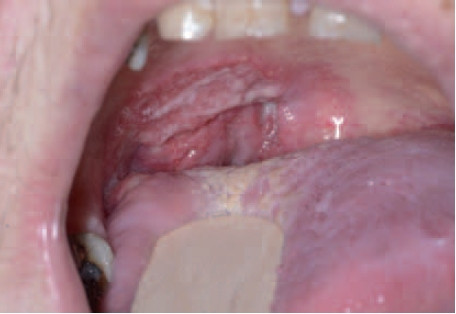

Eenzijdig vergrote tonsil

Een eenzijdig vergrote tonsil is een lymfoom. Bij aanwezigheid van risicofactoren moet de huisarts alert zijn op de mogelijkheid van een onderliggende maligniteit. Infecties of…